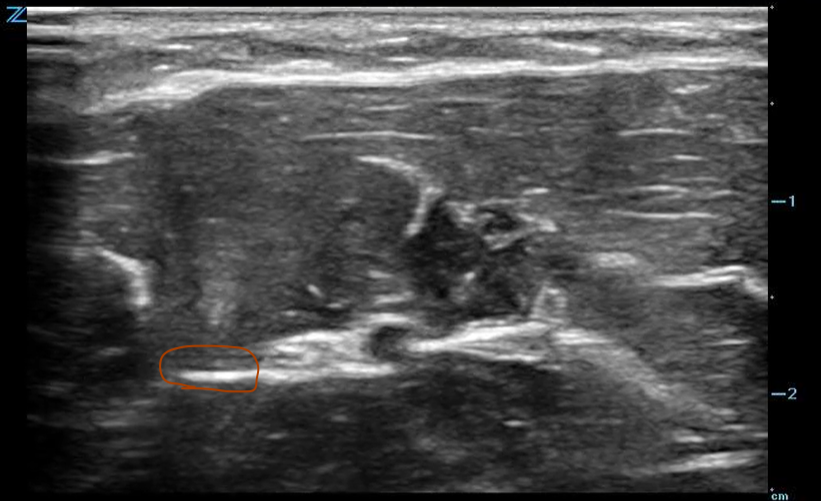

Above is the ulnar nerve next to the ulnar artery. Circled is a fascial plane next to the nerve. By injecting into the fascia you should see hydrodissection through the fascia that spreads to the nerve. This can provide a nice target for more novice users.

To perform the block, start on the ulnar aspect of the wrist and scan proximally. Pay close attention to the ulnar aspect of the artery and you should see a honeycomb like structure become much more prominent as you scan more proximally. Where you exactly block it on the forearm isn’t very important-just do it an area where you feel like you have good visualization.